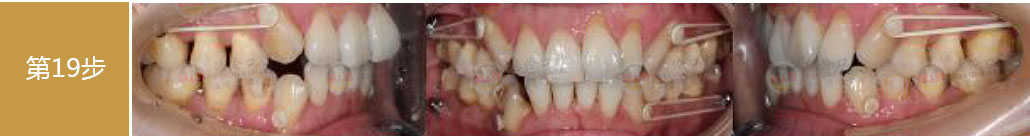

每一周 美一點

每周一次換新 讓牙齒擁有新的改變 每周一點蛻變 讓你遇見更美的自己